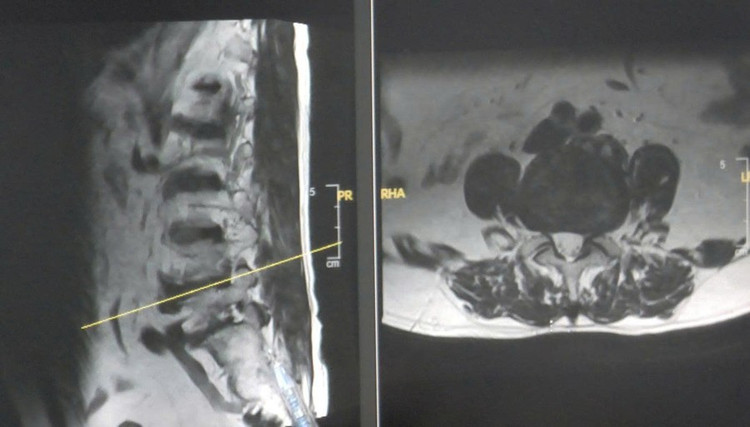

Qua kiểm tra lâm sàng và chụp cộng hưởng từ (MRI) tại bệnh viện, các bác sĩ phát hiện ông L. bị thoát vị đĩa đệm cột sống thắt lưng L4–L5. Khối thoát vị đã tách rời, chèn ép mạnh vào rễ thần kinh tại vị trí ngoài lỗ liên hợp.

Hình ảnh MRI thoát vị đĩa đệm của bệnh nhân. (Ảnh: BVCC)